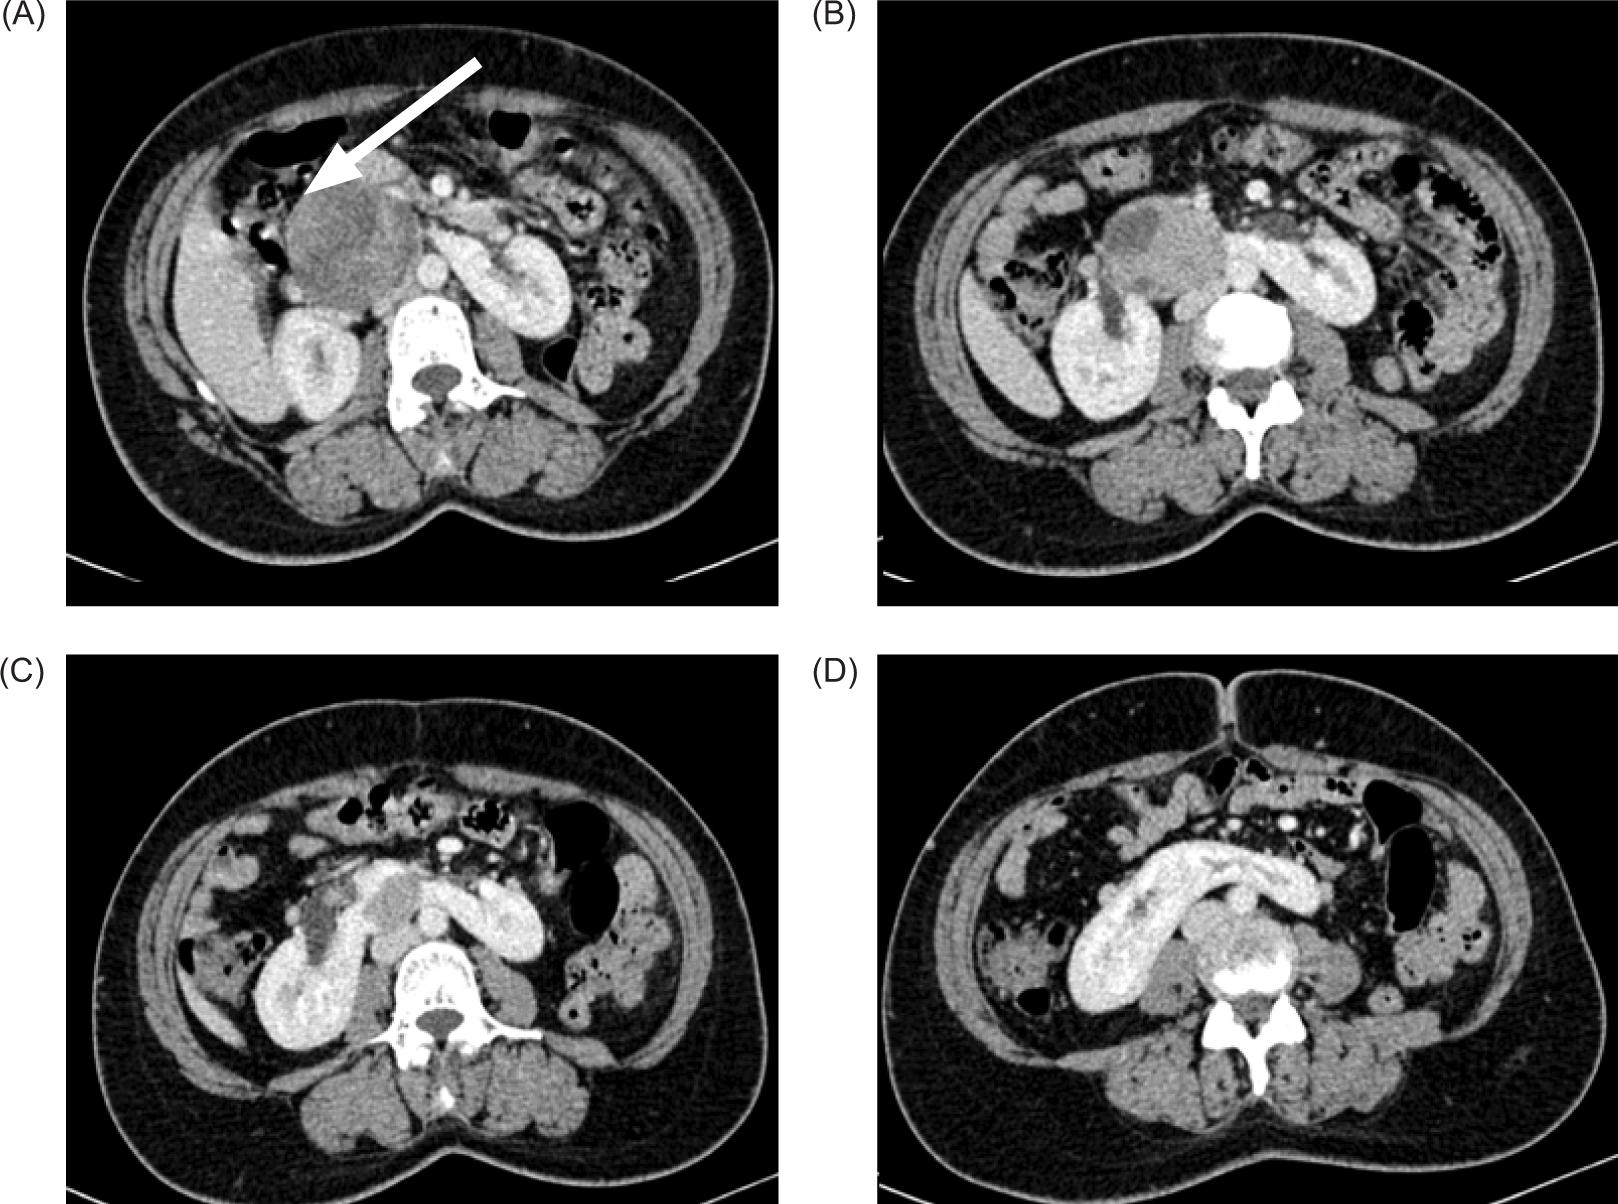

A 43-year-old female patient presented to the Medicine Department complaining of right flank colic that has been persisting for 2 months with a sudden onset and of moderate intensity. The patient also gave history of fever with chills, nausea, and episodes of non-bilious vomiting since 7 days. The patient also complained of burning micturition since 1 month. There was no history of hematuria. No known comorbities were noted. Base-line blood investigations and urine routine examinations were normal. Ultrasound examination of the abdomen revealed HSKs, which were slightly unascended with fusion of both the lower poles of the kidneys by normal renal parenchyma connecting across midline anterior to aorta and inferior vena cava (IVC). A well-defined sold mass of heterogeneous echotexture with few hypoechoic areas within the lesion was seen arising from the upper portion of isthmus (Figure 1).

Figure 1: (A) Left kidney not visualized in the left renal fossa; (B) Well-defined solid mass of heterogeneous echotexture arising from isthmus of HSK.